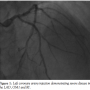

The patient developed pain in the volar aspect of his right arm soon after the guiding catheter was advanced over the J-tip wire. Progressive expansion of a hematoma was noted, and after successful PCI, a peripheral angiogram was performed of the right radial artery, demonstrating a perforation with persistent contrast dye extravasation and soft tissue staining (Figure 2). The bivalirudin infusion was immediately stopped and prolonged balloon inflation using a semi-compliant coronary balloon (Trek, 4.00 mm diameter, 15 mm length;